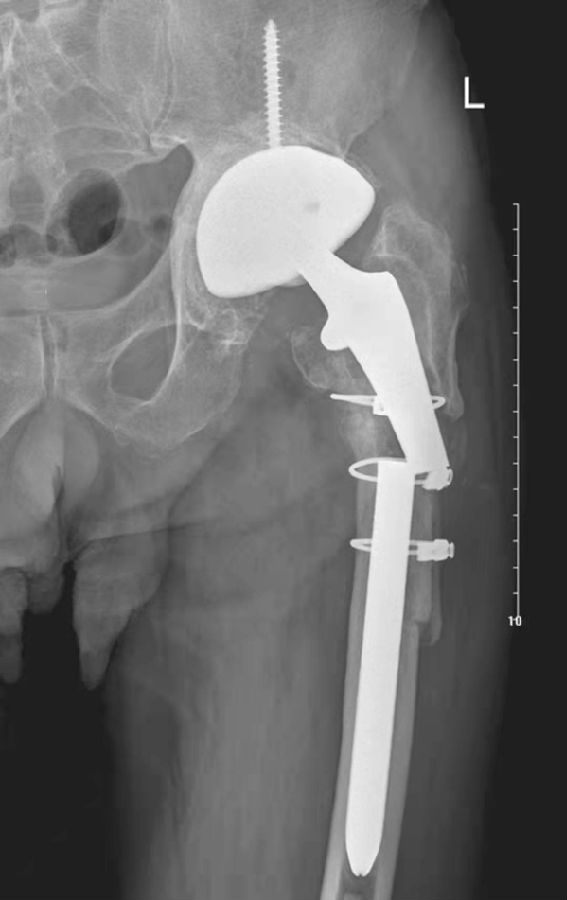

九、术后股骨干骨折

术后股骨干骨折可能发生在术后数月或数年,可有多种不同的原因引起。骨折最多发生于假体柄尖部附近或其近端(图14、图15)。

Johannson将这类骨折分为三型:Ⅰ型骨折发生在假体尖端近侧,不向远端延伸;Ⅱ型骨折从股骨干的近端向远端延伸超出假体柄尖端;Ⅲ型骨折完全位于假体柄尖端的远侧。

图14 人工关节置换术后股骨干骨折

平片,示左侧假体柄尖部附近股骨干骨折并错位